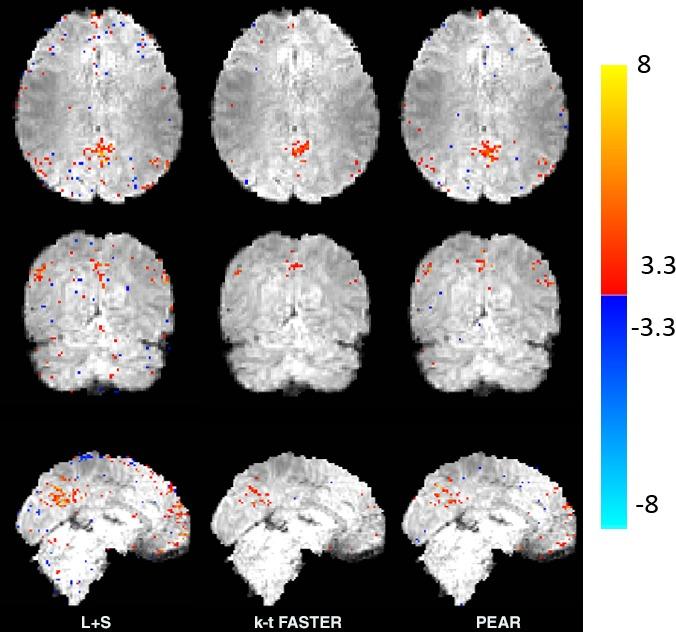

Experimental results include purely synthetic simulation, a simulation with real timecourses and retrospective undersampling of a real fMRI dataset. Evaluation was performed both quantitatively and visually versus ground truth, comparing PEAR to two additional recent methods for fMRI reconstruction from undersampled measurements. Results demonstrate PEAR's improvement in estimating the timecourses and activation maps versus the methods compared against at acceleration ratios of R = 8,10.66 (for simulated data) and R = 6.66,10 (for real data).

This paper presents PEAR, an undersampled fMRI reconstruction approach based on decomposing the fMRI signal to periodic and fixed rank components. PEAR results in reconstruction with higher fidelity than when using a fixed-rank based model or a conventional Low-rank + Sparse algorithm. We have shown that splitting the functional information between the components leads to better modeling of fMRI, over state-of-the-art methods.